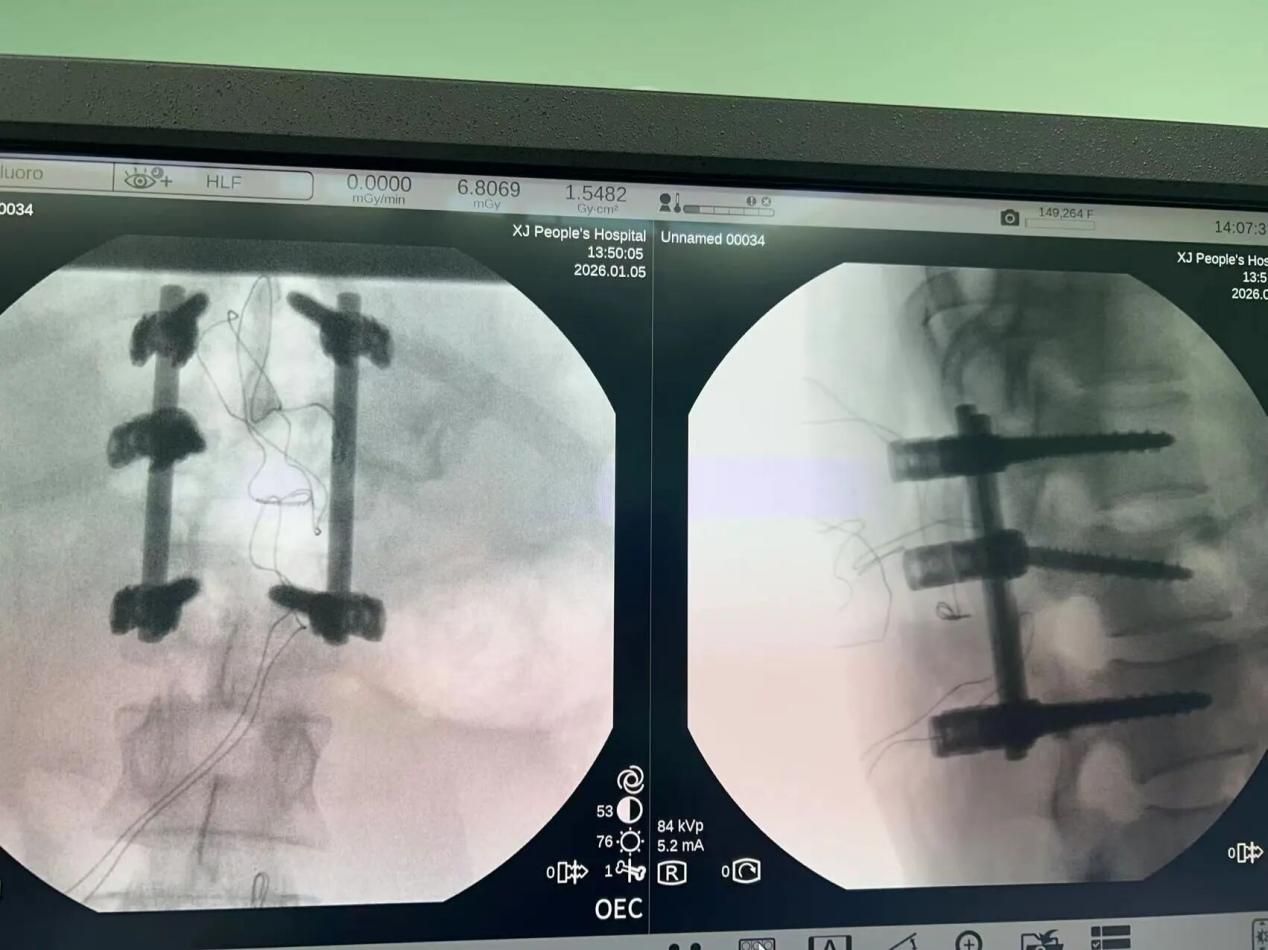

6、多学科携手点亮胸椎骨折患者康复之路

近日,新疆医院骨科,以一场高效、精准的联合救治,驻疆专家樊立宏、王国毓前瞻性地邀请神经内科专家李建新主任协作,引入了 “术中神经电生理监测(IONM)” 这一尖端导航技术。运用躯体感觉诱发电位(SEP)、运动诱发电位(MEP)、自由肌电图(EMG)及触发肌电图等多重技术,构建起全方位的神经功能监护网络。在置入椎弓根螺钉的关键时刻,触发肌电图敏锐判断,规避神经损伤风险;在骨折复位与减压的精细操作中,SEP与MEP的波形犹如生命律动的密码,被实时解读,任何细微异常都即刻化为语音提示,引导手术医生调整手法,最大程度保护脊髓功能毫发无损。为一位胸椎爆裂骨折危重患者托起了希望的脊梁。